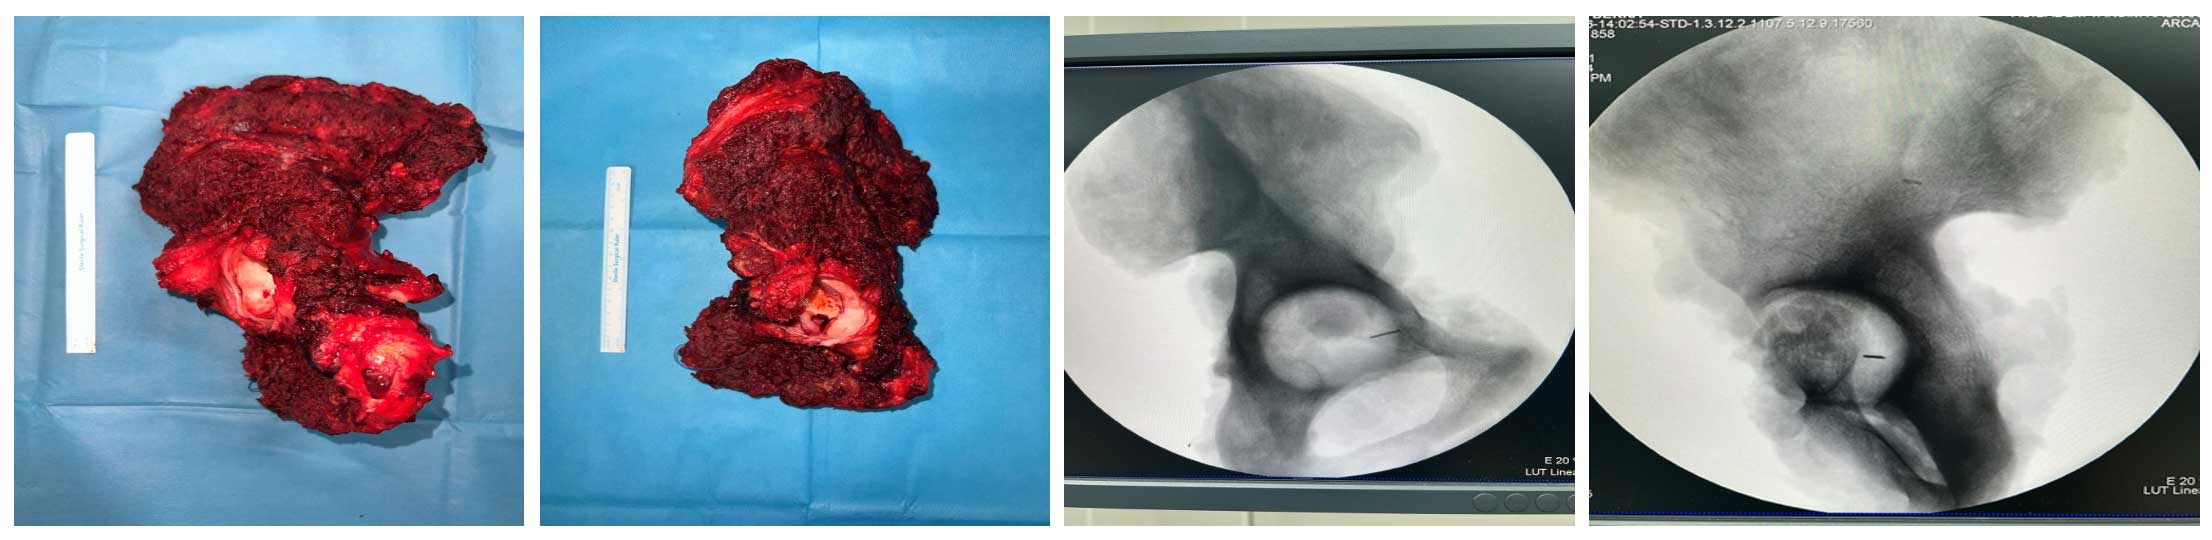

Ameliyat Esnası: Rezeksiyon dokusunun klinik ve skopi görüntüsü.